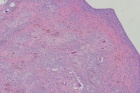

K.T. - 28 year old female with intermittent left hip pain for several years; she began having more frequent and intense pain a few months ago, prompting her to seek treatment

Zoom image: Cell stain Cell stain.